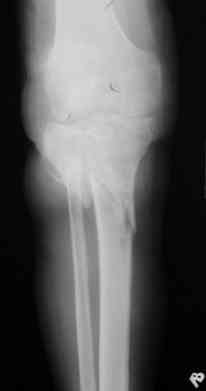

Р-граммы за март и апрель

Р-граммы и фото за 4.05.2007 - 7-е сутки после операции.

Ход операции - линейным разрезом по передней поверхности голени обнажена зона ложного сустава большеберцовой кости. От кости отсепарованы медиально м/ткани. Из зоны ложного сустава убраны рубцовые ткани, мобилизован дистальный отломок. По передней поверхности удалены два осколка, связанных грануляциями. Произведено удаление грануляционной ткани из проксимального отломка (на вид сине-серого цвета), "чистого" гноя не было. Затем произведено наложение аппарата и репозиция отломков. По передне-медиальной поверхности образовался дефект до 4х2х2 см + полость в проксимальном отломке. Удаленные осколки очищены от грануляций, уложены в место дефекта, зажаты между отломками. После иссечения раны по передней поверхности, находящейся рядом с операционной раной, последняя ушита с большим натяжением.

Перелом мыщелка сросся. Проксимальный отломок очень порозный.

На перевязках - из раны небольшое кол-во сукровичного отделяемого. Отек голени умеренный, состояние кожи на фото.

Аппарат видел, репозиции не заметил. О "наложенном" аппарате: спицы в проксимальном отломке б\берцовой кости проведены очень низко, и опять только две, как и в первом аппарате. Почему только одна спица в дистальном парафрактурном кольце? Проксимальная база на бедре должна улучшить стабильность проксимального фрагмента tibia? Ничего подобного двумя спицами в одной базе при таком длинном рычаге вы не добьетесь, а вот совсем потерять движения в коленном суставе они почти гарантируют.

О репозиции: мыщелок сросся и слава Богу, но основные отломки фиксированы в вальгусном положении, собственно как и было, это критично. В чем состояла репозиция?